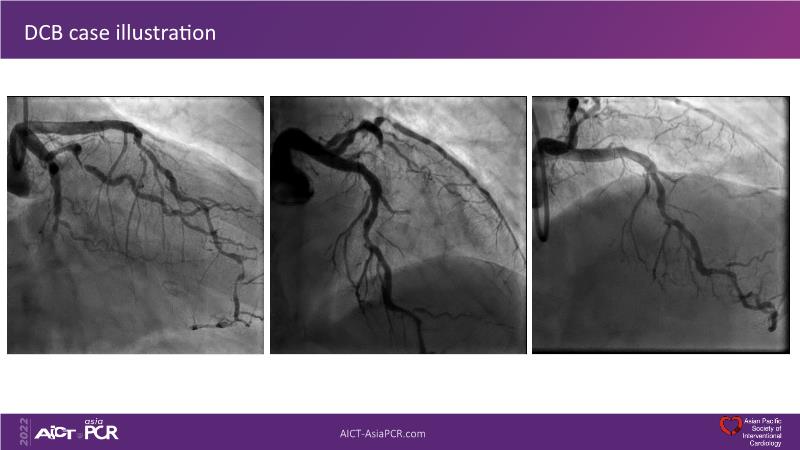

Consult this session to understand the technology and scientific evidence of the novel sirolimus drug-coated balloon, to learn its utility for PCI in a variety of lesion and patient subsets and to understand the evidence and outcomes in real-world patients.

- To learn the utility of the DCB for PCI in a variety of lesion and patient subsets

- To understand the evidence and outcomes of this DCB in real world patients